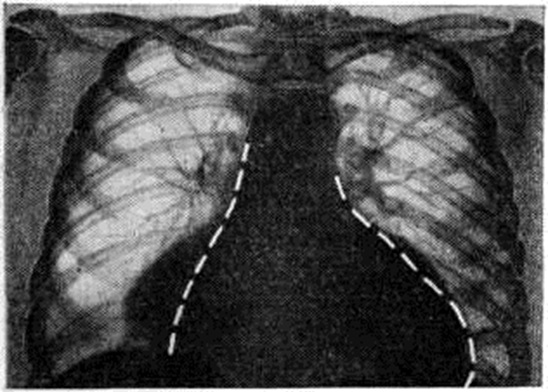

Рис. 2.

Рентгенограмма грудной клетки больной первичным гипотиреозом с явлениями гидроперикарда: пунктиром указаны границы сердца через 2 месяца после начала лечения тиреоидными гормонами.

Рентгенологическое исследование выявляет изменения в сердце и желудочно-кишечного тракте. Рентгенологическое картина сердца характеризуется значительным увеличением его размеров, медленными и вялыми сокращениями. Нередко обнаруживают наличие жидкости в перикарде, исчезающей или значительно уменьшающейся в процессе заместительной гормональной терапии (рисунок 2). В желудочно-кишечного тракте — понижение моторики кишечника и отёк слизистой оболочки. Костная система у взрослых при Гипотиреоз не нарушается.